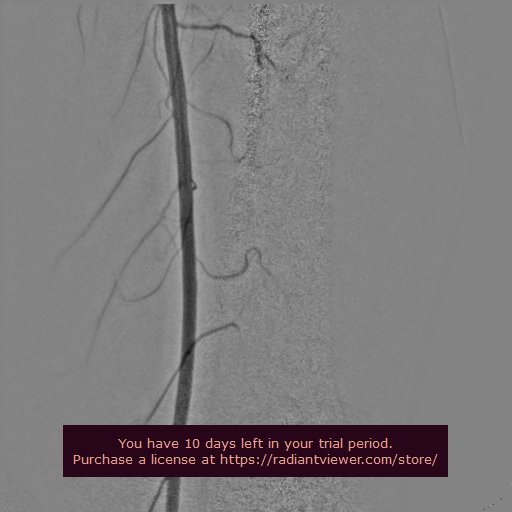

SUPERFICIAL FEMORAL ARTERY ANGIOGRAM

POPLITEAL ANGIOGRAM